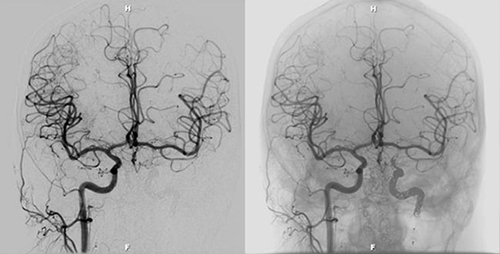

What exactly is neurointerventional radiology you might ask? Neurointerventional radiology is a subspecialty of IR that uses minimally invasive, endovascular procedures aimed at preventing strokes, cerebral aneurysms and other life threatening conditions of the central nervous system. These procedures allow physicians to see inside the brains of their patients much like a superhero; moreover, conducting these procedures requires a hand more steady than superman. The procedure is performed by inserting a catheter in the groin area of the patient. From there, the physician slides the catheter through the femoral artery into the aortic arch of the heart. The catheter is then strung through the carotid artery and into the vascular system of the brain where physicians use radio imaging to visualize what exactly is occurring inside. Daniel says of the procedure, "You are actually inside the vascular system with the catheter and you can use that to do various things—a lot of the time, what they are inserting is a stent, which can expand an occluded artery and allow blood to flow to the affected portion of the brain. If you have someone who has had an aneurism and there is a risk of rupturing, they can insert a coil which…basically allow clots to form around them in the aneurism, closing it off so that the blood pressure doesn't continue to push it…it keeps it from rupturing and keeps the patient from having a hemorrhagic stroke. They deal a lot with strokes and preventing those by either opening up vessels or preventing vessels that are about to break from breaking." Watching the procedure being conducted is something like a video game and just being in the lab evokes the feeling that something very cool is about to happen. Daniel describes the thrill of experiencing it firsthand saying, "They have the neurointerventional radiologists suite where they have probably eight big computer screens up on this display which they can move around…they have machines where they can have the x-ray spin 360 degrees along different planes around the person's head and can create a three-dimensional image and basically thread in the catheter and watch it go through with live time x-rays, like a videogame on the screen, following it up to where it needs to go. It's pretty neat." For many, describing the experience as 'pretty neat' would be an understatement.

Image of Cerebrovascular System, ©Texas Radiology Associates